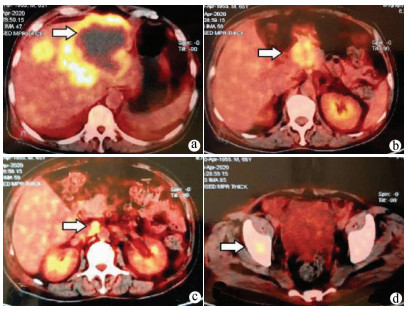

Anti-PD-1 monoclonal antibody combined with apatinib in treatment of rare primary squamous cell carcinoma of the liver: A case report

Yuchen FEI, Donglai LYU

2021, 37(3): 670-672. DOI: 10.3969/j.issn.1001-5256.2021.03.032

Abstract(870) HTML (228) PDF (2972KB)(48)

Abstract: